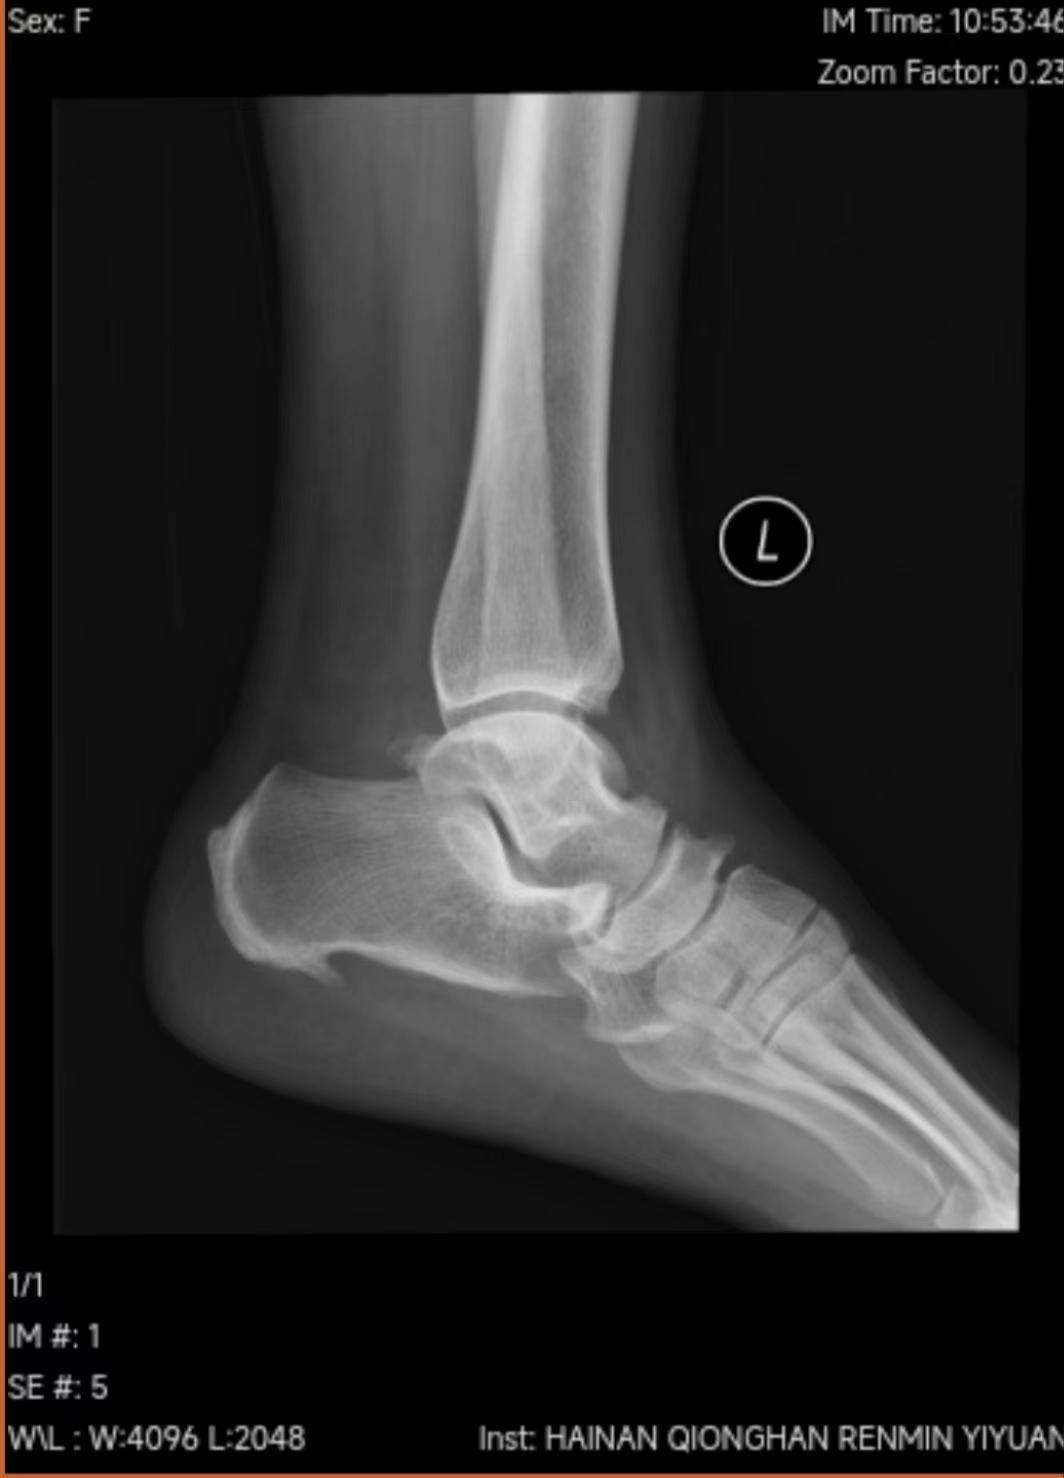

(琼海市人民医院骨关节外科供图)